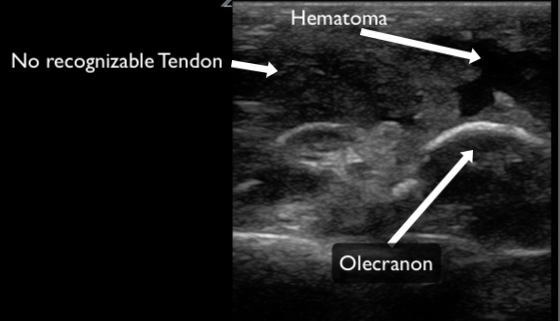

Tendons should be interrogated in their entirety in the short and long axis to where they insert into the bone. The region adjacent to bony insertion is where the majority of pathology is identified. Complete or partial ruptures are readily apparent as disruption of normal striated tendon fibers often with associated surrounding hematoma (Figures 11, 12 & 13). Range of motion testing with simultaneous ultrasound can assist in evaluation for complete ruptures. Tendinopathy can be identified by the presence of calcifications (Figure 14), edema (Figure 15), and increased vascularity (when compared to the contralateral tendon). Edema will make the tendon more hypoechoic and larger in diameter compared to the contralateral tendon.

Figure 13. A triceps tendon evaluated in the long axis demonstrating a complete rupture. There is no discernable tendon and obvious hematoma present.